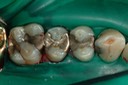

Kyle Chock #14 pre-op

Kyle Chock #14 caries removal

Kyle Chock #14 prep